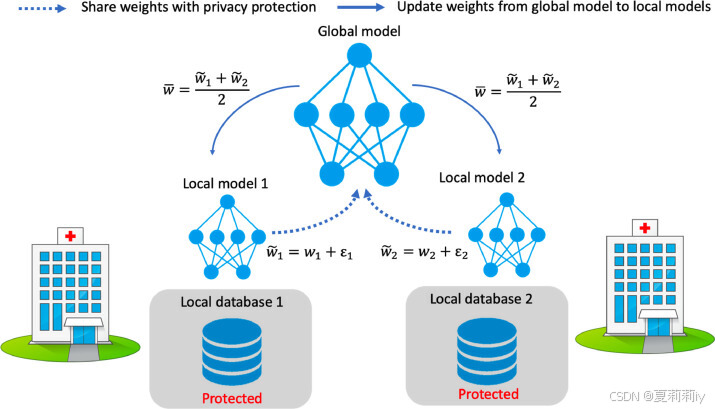

(2)Privacy-preserving decentralized training

②Training process:

(3)Randomized mechanism for privacy protection

④Gaussian Mechanism: adding noise to

They employ Laplace Distribution with scale :

and , the

noise will be add to

, the difference privacy is